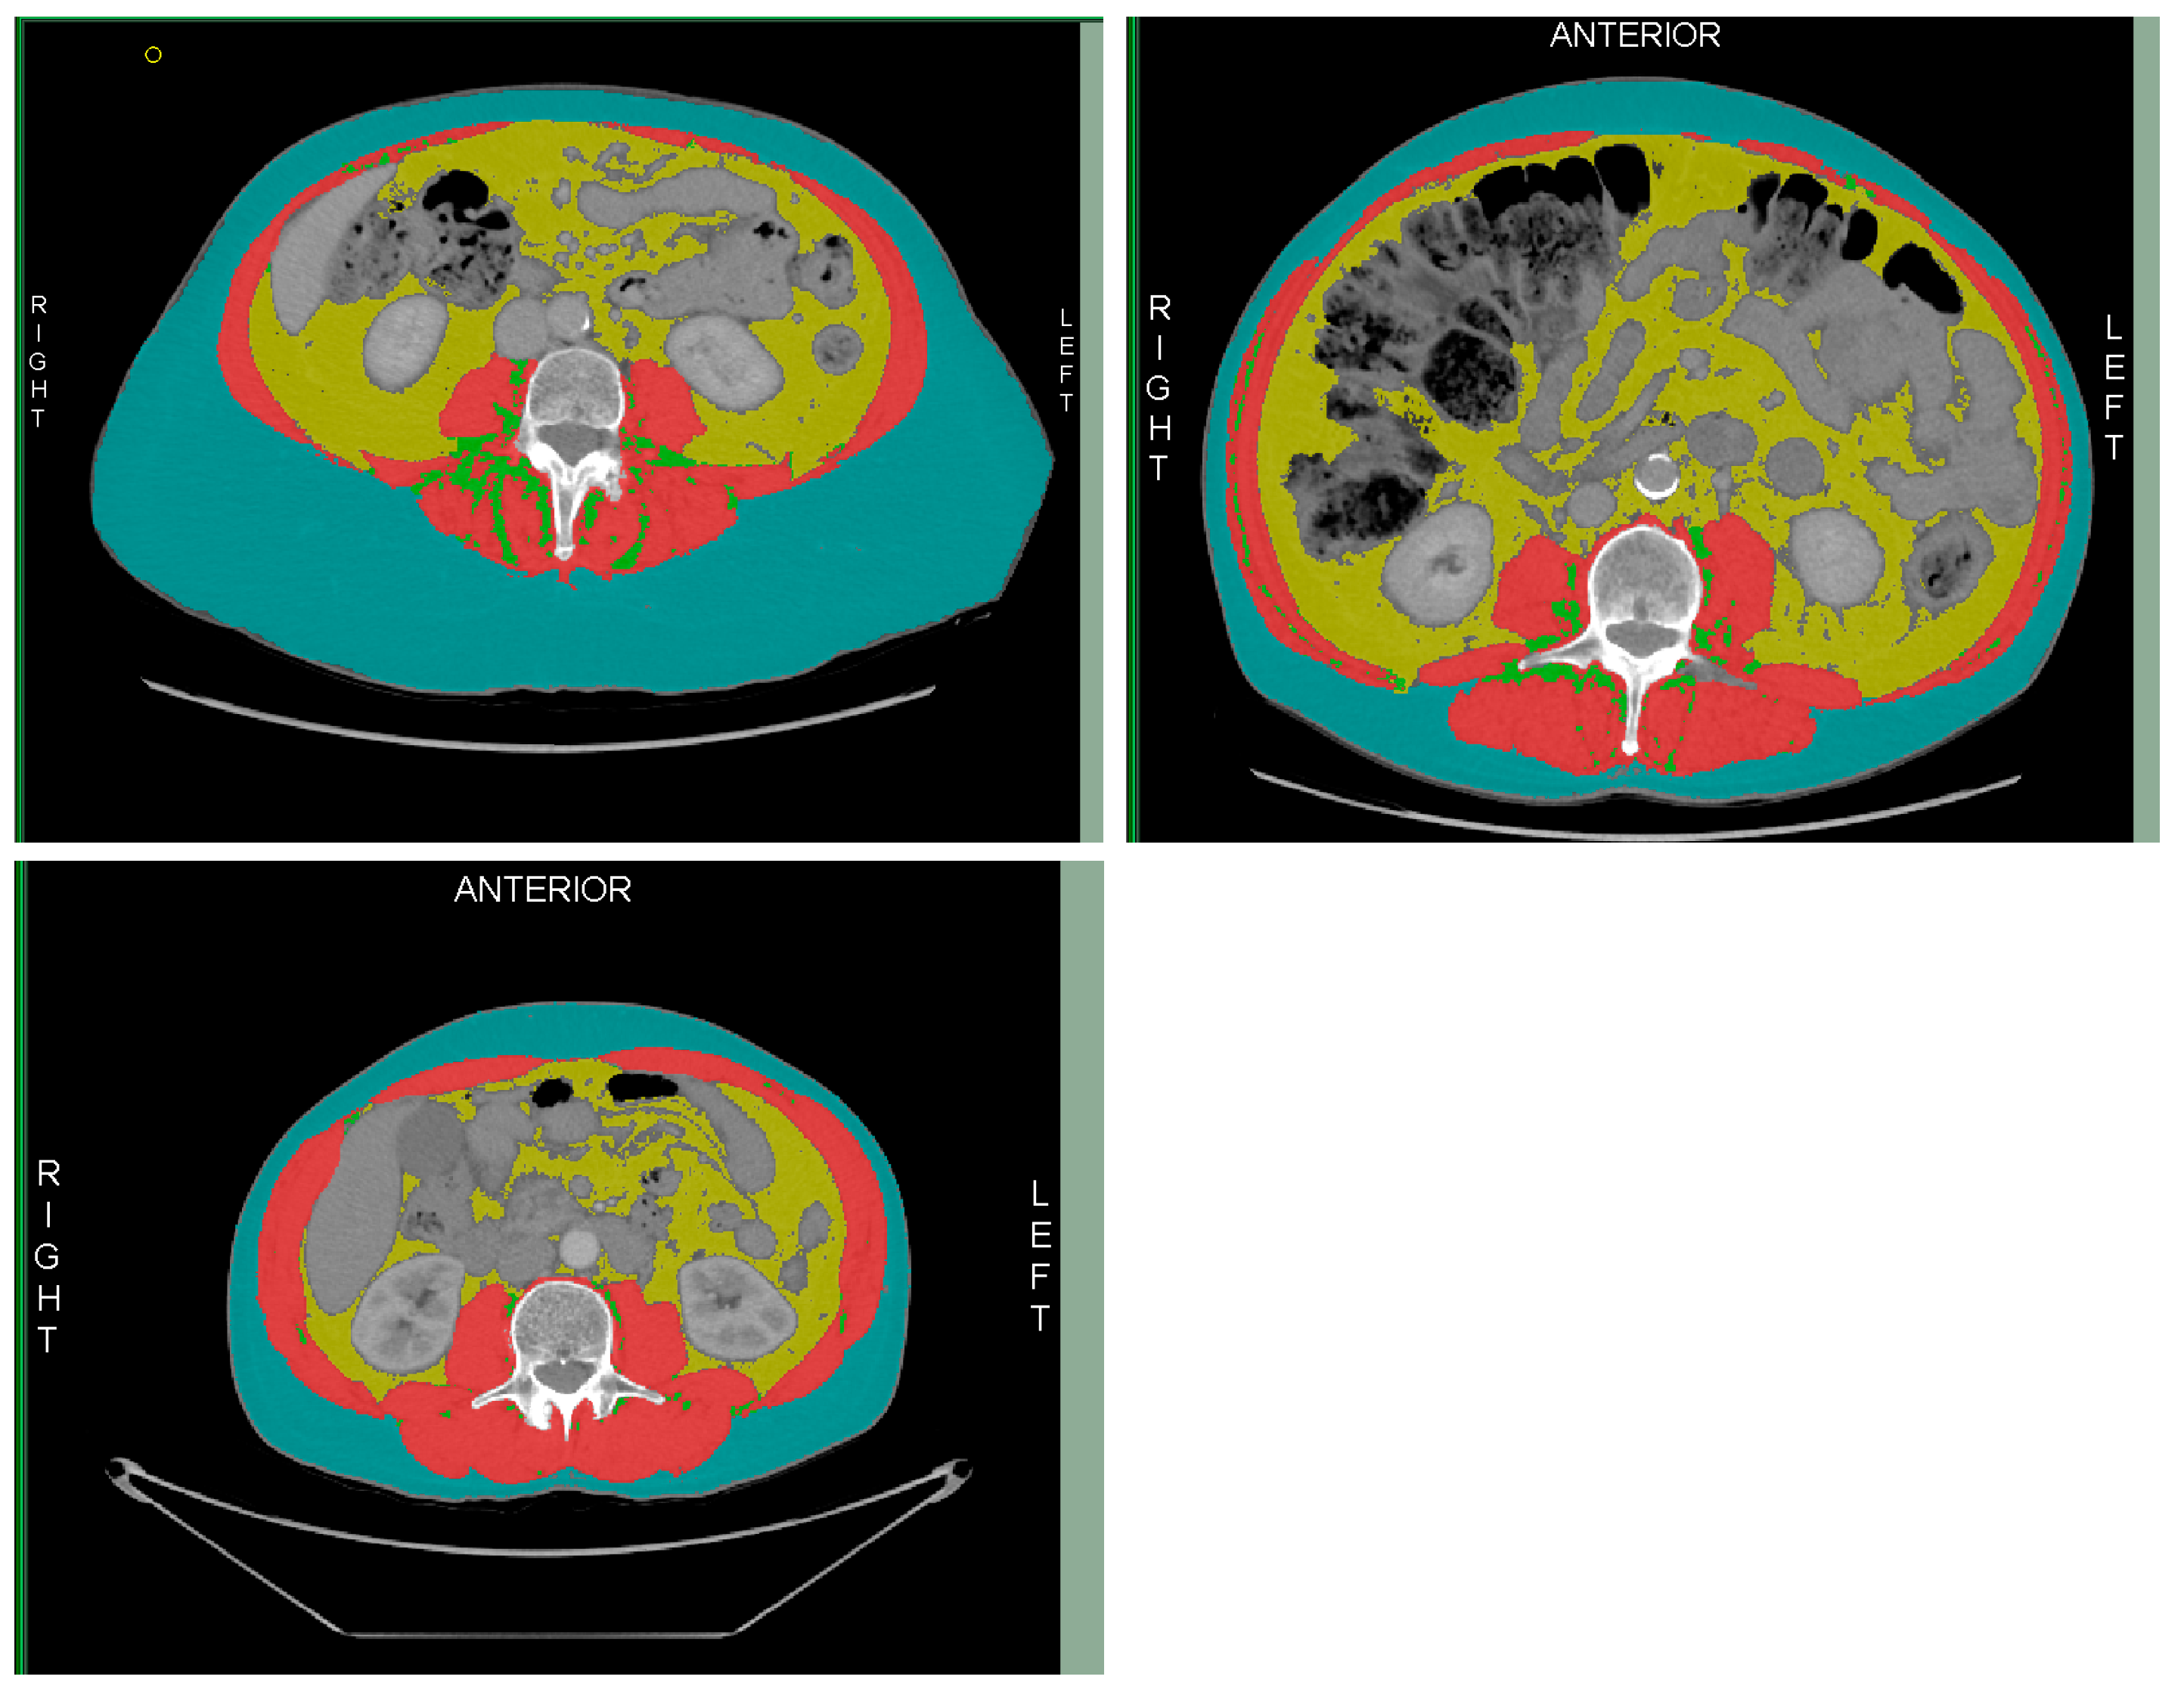

- Tomovision. Slice-0-matic Alberta Protocol Users Manual. 2017. Available online: https://tomovision.com/Sarcopenia_Help/index.htm (accessed on 11 February 2024).

- Byrne, C.A.; Zhang, Y.; Fantuzzi, G.; Geesey, T.; Shah, P.; Gomez, S.L. Validation of skeletal muscle and adipose tissue measurements using a fully automated body composition analysis neural network versus a semi-automatic reference program with human correction in patients with lung cancer. Heliyon 2022, 8, e12536. [Google Scholar] [CrossRef]